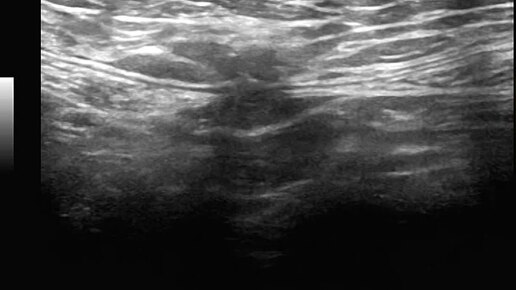

Видео к статье "Общие принципы ультразвуковой диагностики наружных грыж живота" Адрес: https://dzen.ru/a/Z2k58ScRsjQP-dA9